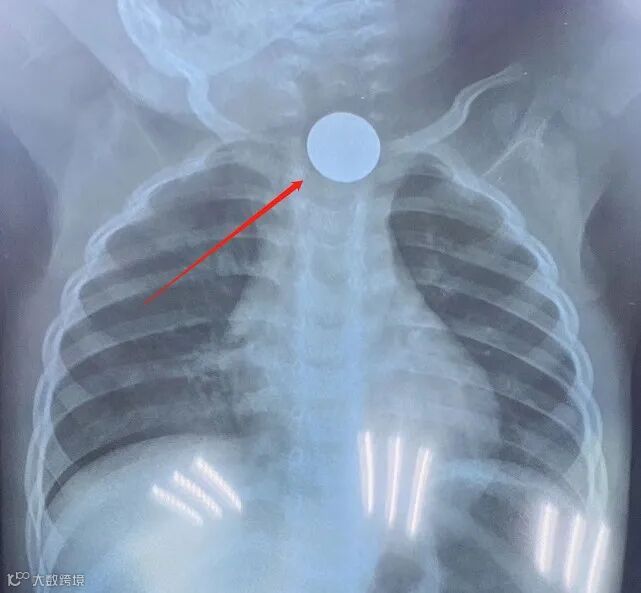

近日,一名一岁半男童在家自己误吞了一枚1角钱硬币,两天内家长都没有发现,因男童出现吞咽困难,进食呕吐,遂送来市人民医院急诊科就诊,拍胸片时才发现硬币卡在男童食道里。就医后,值班医生肖静主治医师运用Foley导尿管法取圆形食道异物,用一根10号儿童导尿管,一分钟时间就将卡在男童食道里2天的硬币取出。